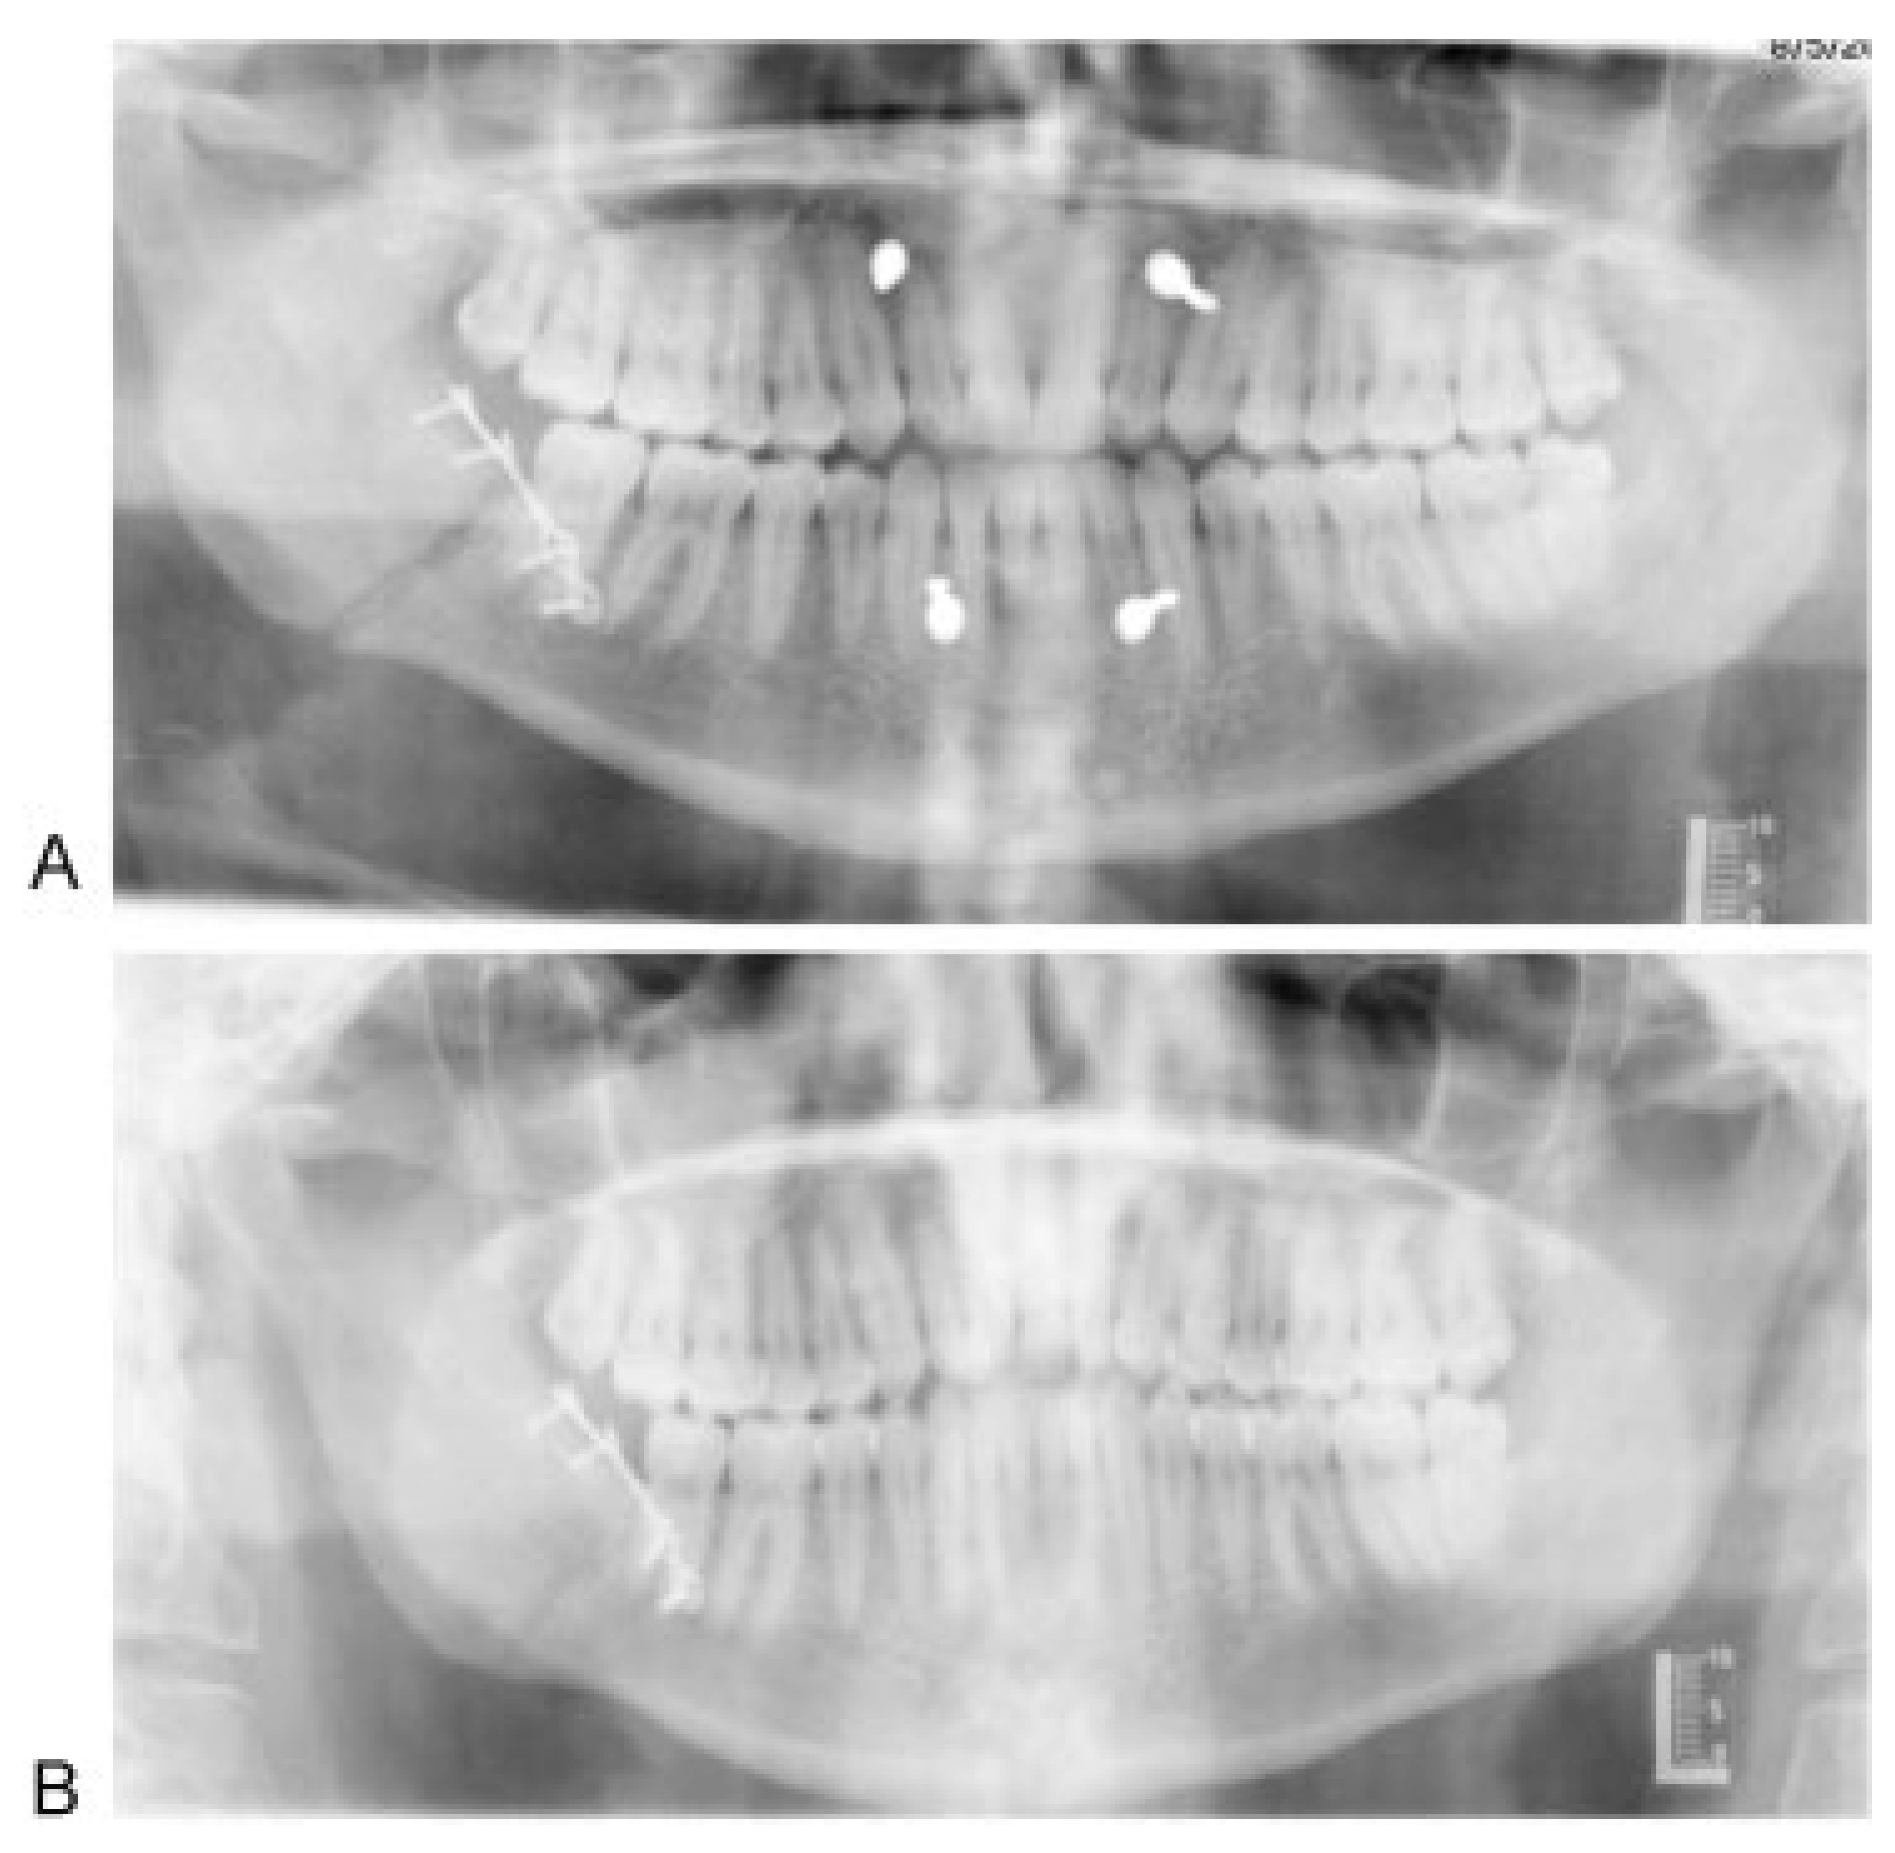

1.2. Surgical Technique